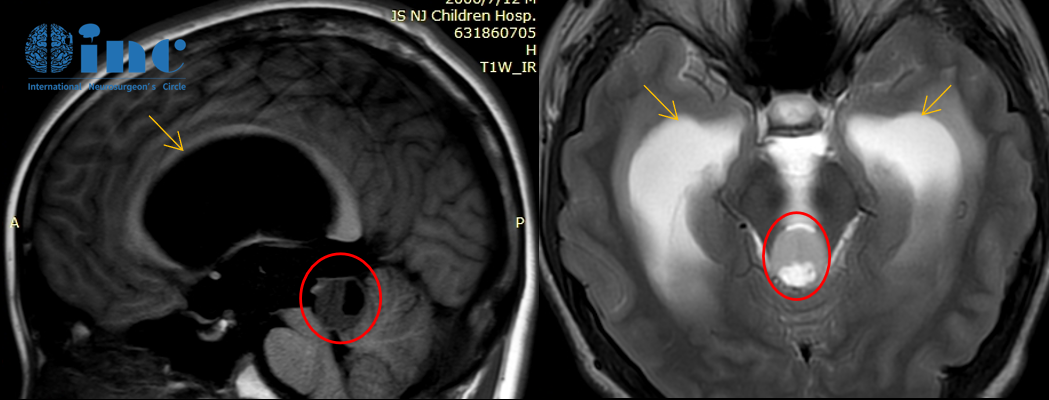

“每次都说毛细胞星形细胞瘤一般不长,观察就行,但是后来我最后一次去找他们的时候,我和医生说症状太重,不行就做手术,他们最后和我说实话,因为做手术风险过大,所以说建议你观察……”14岁的小永一家就遇到类似的问题。

孩子查出脑干胶质瘤,头晕、头痛、梗阻性脑积水……父母永远是最焦心的,对于治疗他们也是希望尽快为孩子解除病痛。谁愿意孩子脑子里一直有一个可怕的肿瘤呢,孩子还小,肿瘤总有长大的机会。但是没人愿意为孩子做手术,为人父母恨不得自己能代替孩子受苦,可是偏偏爱莫能助,总不能自己做手术吧……

就这样一直等,这一等就是2年多,孩子的病情越来越严重。得知孩子无法再等时,他们下定决心尽一切努力为孩子争取好的治疗,保证孩子术后能够正常生活和学习。当一家人找到了巴教授,并得到了教授认为可以手术的详细评估时,最终成功手术。平安度过了术后的第一年,然后是第二年、第三年、第四年……我们也见证着他慢慢长大,成为优秀的人!